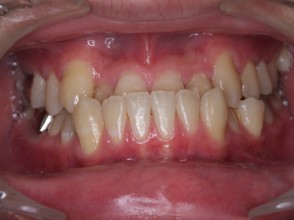

矯正治療・根管治療・補綴治療の症例紹介(三隅歯科クリニック)

症例詳細

| 主訴 | 過去作成した右下の被せ物がずれて入っており、たまに腫れる。歯並びも気になる。 |

| 治療内容 | 矯正治療を行いました。 |

| 治療費 | 800,000円(税込み) |

| 治療期間 | 2年半(矯正治療期間 2年) |

| 治療回数 | 30回 |

| 想定されたリスク | 術前に基礎資料を整え分析し、セットアップモデル等でシミュレーションをしておかないと、予定通りの治療が行えないリスクがあった。 |